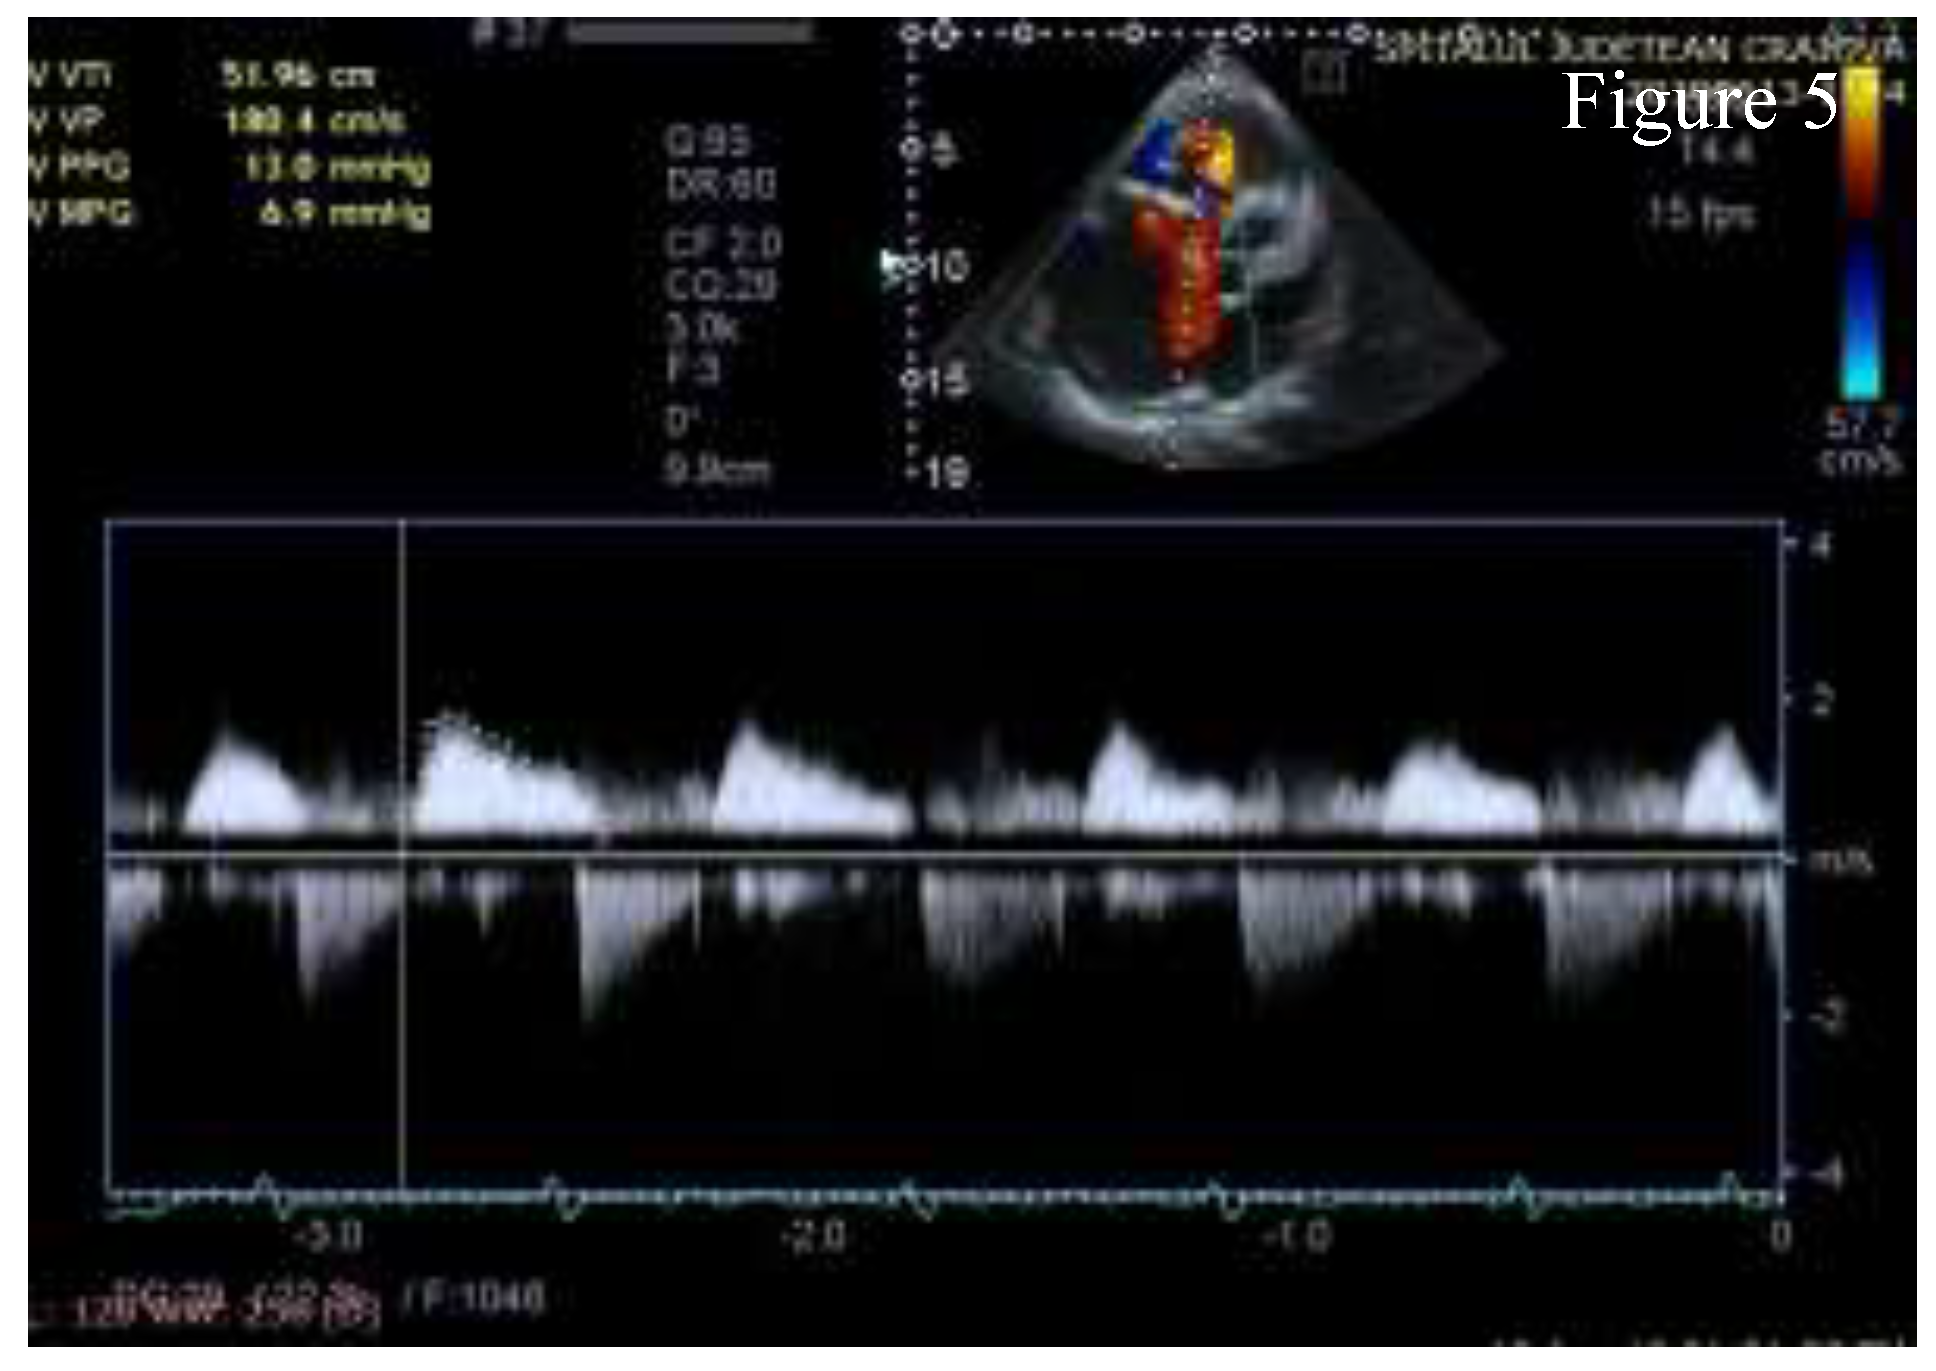

Figure 5.

A4C CWD - the envelope of right ventricular inflow with high gradients indicating severe tricuspid stenosis and the envelope of severe tricuspid regurgitation.